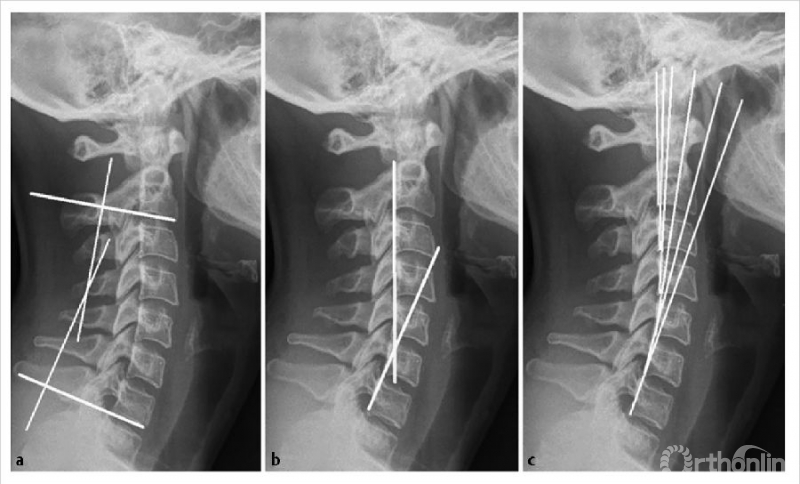

颈椎前凸(CL)在影像学上测量为一个负角度,而后凸是一个正角度。如图7所示,测量颈椎前凸的方法有多种:改良Cobb法(mCM)、Jackson生理应力线(JPS)、Ishihara指数和Harrison后切线法(HPT)2,9。

所有的测量都可以用颈椎的X光或CT扫描的矢状面来获得。mCM(图7a)的计算方法是先沿着C2和C7的椎体下终板画线,然后画垂直于两者的垂直线,垂直线相交处形成的角度即为颈椎前凸角。JPS(图7b)是沿着C2和C7的椎体后缘绘制的两条线的交点10,11。HPT(图7c)通过绘制平行于C2到C7椎体后缘的垂直线来计算,加上所有节段的角度。

图7 矢状位X线片显示用于测定颈椎前凸的改良Cobb法(a)Jackson生理应力线(b)Harrison后切线(c)(经Scheer等允许使用2)